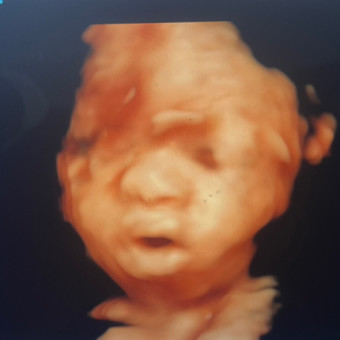

Kalyn and Tj baby registry💙

Kalyn & Thomas Young & Thomas Young Jr

April 19, 2026

Hello all We are excited to be having our first baby boy. Thank you in advance for all the love support and gifts !